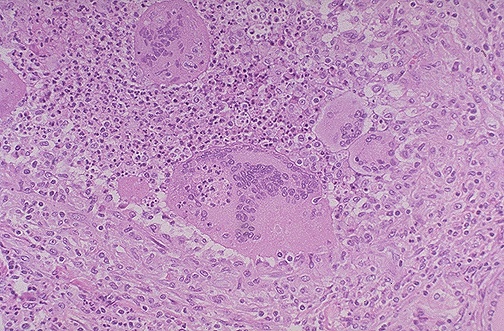

| This is subacute granulomatous thyroiditis (DeQuervain disease), which probably follows a viral infection and leads to a painful enlarged thyroid. This disease is usually self-limited over weeks to months, with transient hyperthyroidism and/or hypothyroidism, and affected patients return to a euthyroid state. Note the presence of large foreign body giant cells with inflammatory destruction of thyroid follicles. |